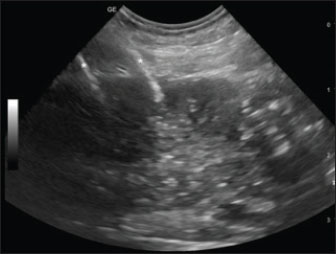

Based on the staging results, the primary tumor and locoregional metastasis were treated with percutaneous ultrasound-guided ECT (Fig. 1), after the administration of intravenous bleomycin and with dogs under general anesthesia and with adequate analgesia.

Fig. 1. Sagittal ultrasonographic image of a patient with neoplastic prostate. Right paramedian longitudinal scan, with a cranial orientation of the ultrasound marker (left side of the image). The right and left prostatic lobes are visualized along the near (superficial) and far (deep) aspects. A portion of the large intestine is visible caudally to the prostate. Despite relatively well-defined margins, the gland shows diffusely mild hypoechogenicity and coarse heterogeneous echotexture. Two hyperechoic lines (asterisks) located at the cranial and mid-levels of the right lobe correspond to the 45-S shielded electrodes inserted percutaneously.